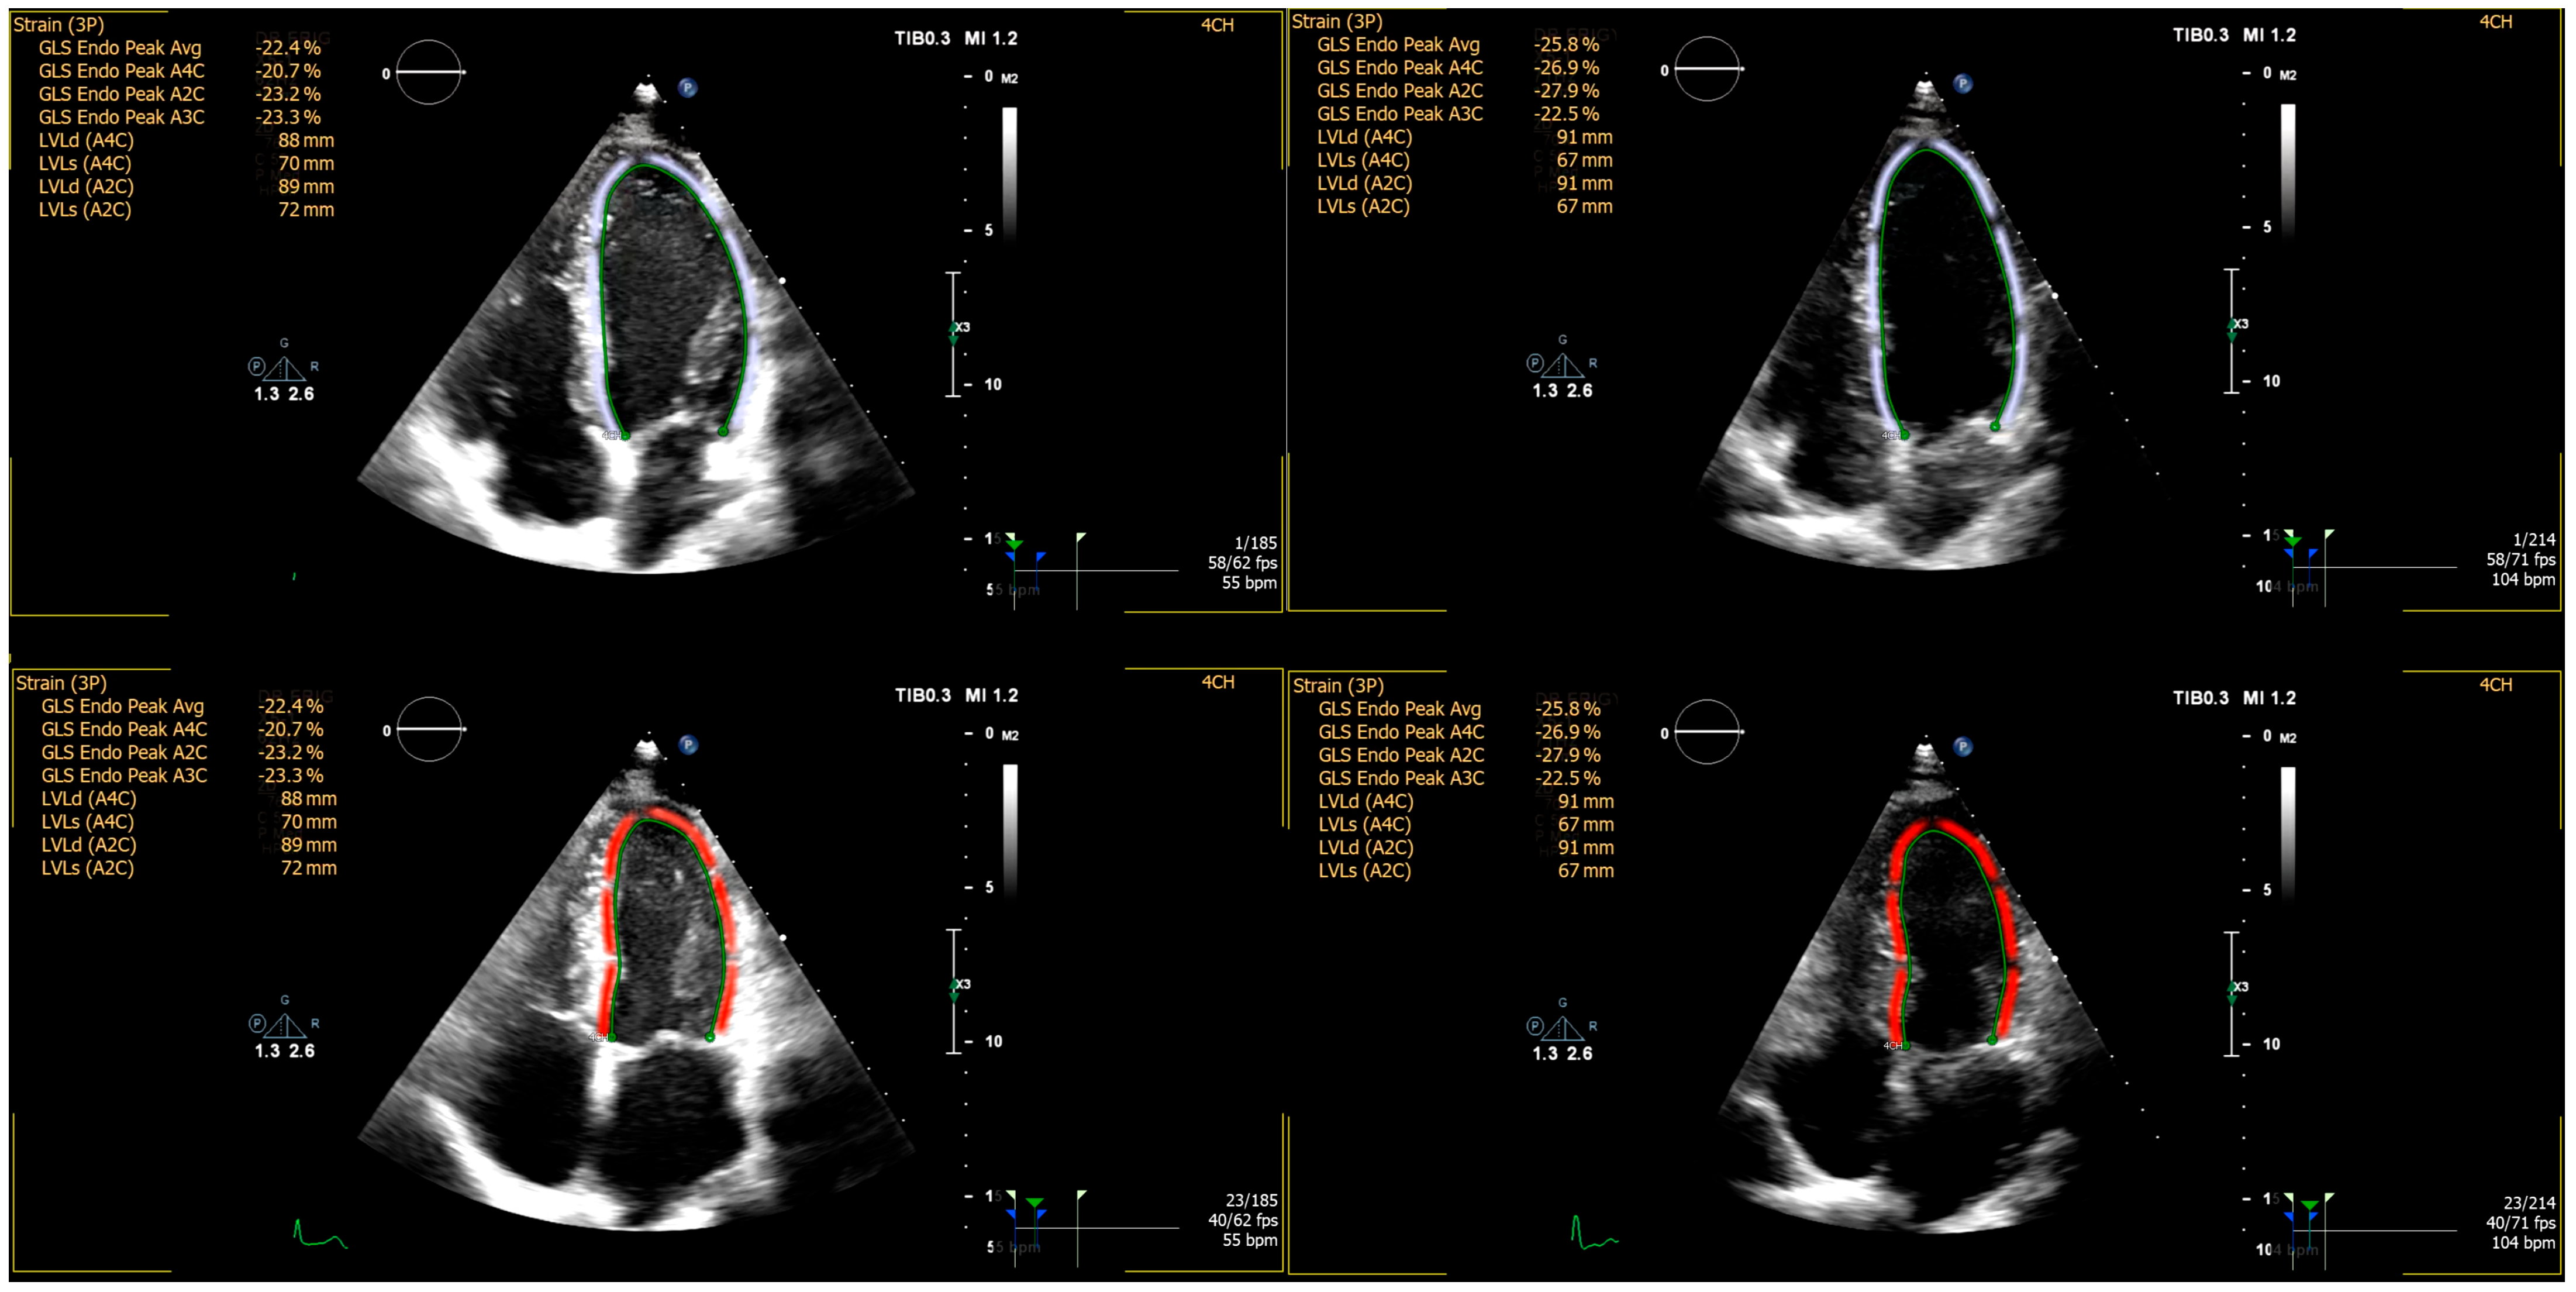

2.2. Echocardiographic Imaging and Analysis

| GLS | −23.0 ± 1.3 | −22.5 ± 1.3 | 0.177 |

| GLS | −24.8 ± 1.7 | −22.3 ± 1.7 | 0.262 |

| Δ GLS | −1.7 ± 1.5 | 0.2 ± 1.5 | 0.652 |